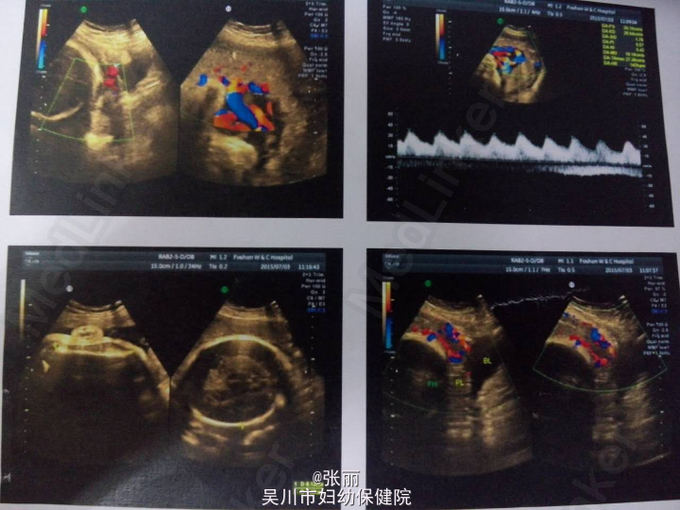

查体:宫高32cm,腹围102cm,宫口未开,胎膜未破。2015-07-03我院B超:单活胎,头位,胎盘低置前壁胎盘下缘距离宫颈口约2.7cm,合并部分胎盘植入可能。BPS8分,S/D1.8。

诊断:1、孕37+5周,单活胎待产,2、前置胎盘,植入可能。3.疤痕子宫 处理:完善MRI处理,检测胎心,注意腹痛及阴道流血情况,择期剖宫产,向孕妇及其家属交代有大出血,子宫切除等风险,积极备血。